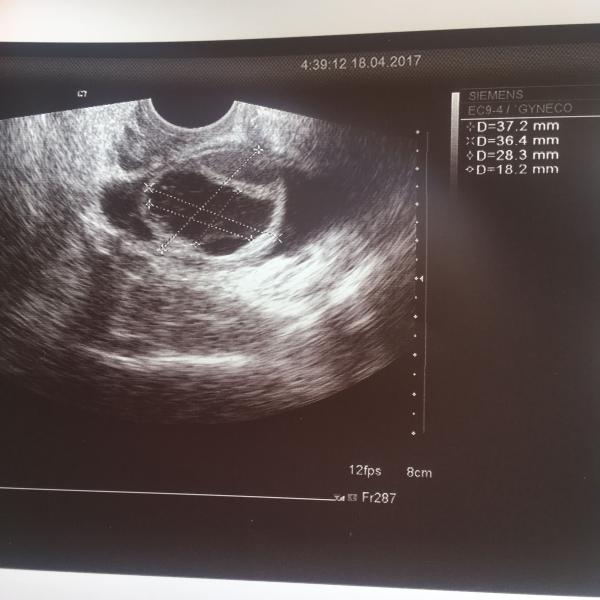

Помогите разобраться, девочки!!! Цикл у меня 25-28 дней. На УЗИ 21 д.ц. образование диаметром 28 мм. Г назвала кистой и сказала, что овуляции не было. Посмотрите фото, пожалуйста, по вашему опыту, это вероятней всего киста или ЖТ так может выглядеть?

@whaleana, спасибо за подробный ответ, выходит у меня в одном цикле 2 кисты в разных яичниках появились. На 5 д.ц. на УЗИ в правом яичнике был фолликул уже 14 мм., ( из-за задержки в предидущем цикле), а сейчас он 20 выходит, или это другой уже...В левом маленькие фолликулы были. Буду сдавать гормоны... А в кистах кровоток должен наблюдаться, не знаете?

@alinkinayaya, да - желтое тело. Я так понимаю, оно круглое должно быть? Может это лопнувший фолликул... но она назвала это кистой.